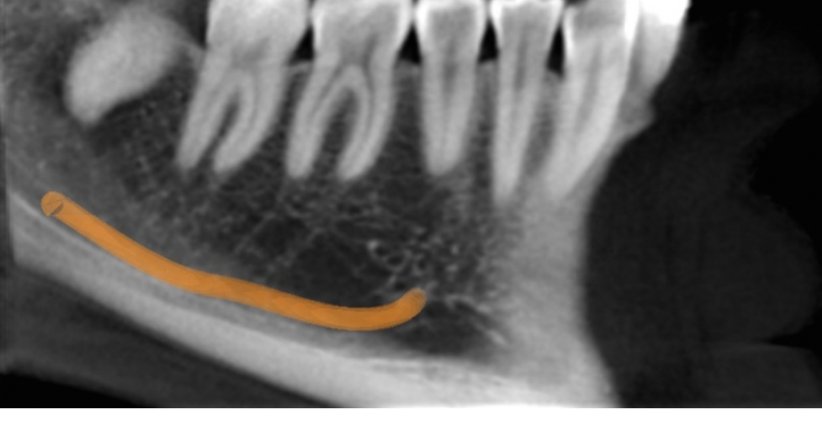

Dieses Gerät ermöglicht neben digitalen 2D-Zahnpanoramaaufnahmen mit variabler Fokuszonentechnologie auch die Durchführung von Aufnahmen mittels 3D-digitaler Volumentomographie (DVT).

• Planung von Zahnimplantaten

• Kiefer/Zahn Erkrankungen

• Kiefergelenke

• Nasennebenhöhlen